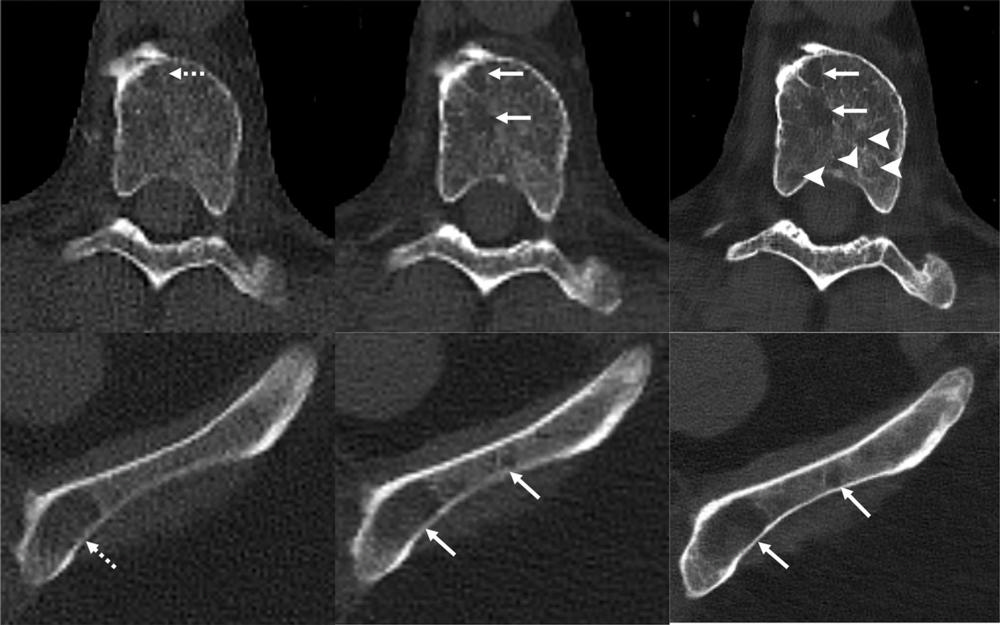

Figure 5. Images in a 71-year-old man with multiple myeloma. Lytic lesions (dashed arrows) within a thoracic vertebral body and the left iliac wing are more conspicuous on the noncontrast-enhanced axial photon-counting detector (PCD) CT image (middle; solid arrows) compared with noncontrast-enhanced axial energy-integrating detector CT image (left). With 0.6-mm Br76 noncontrast-enhanced axial PCD CT reconstruction images (right), more lesions were detected (arrowheads).